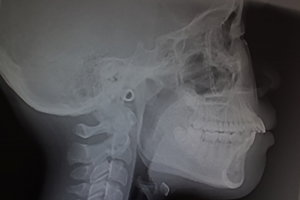

顎関節症(がくかんせつしょう)とは、あごの関節やその周りの筋肉にトラブルが起こる病気のことです。

顎関節症とは、あごの関節や周囲の筋肉に不調が生じ、口が開きにくい、あごの痛み、関節音などの症状が現れる疾患です。原因は一つではなく、噛み合わせの不具合や片側だけで噛む癖、歯ぎしり・食いしばりによる筋肉や関節への負担、ストレスや心理的緊張、長時間のスマホ・パソコン作業などによる姿勢の悪化、さらには外傷やケガなど複数の要因が絡み合っています。